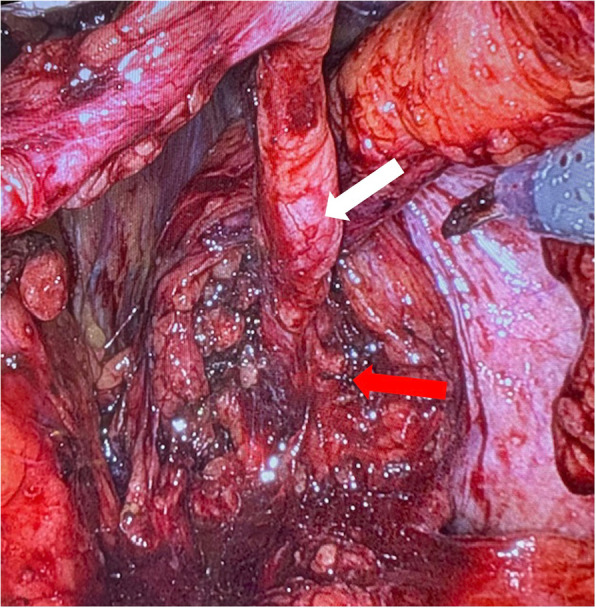

简介和重要性:“先天性肾脏和尿路异常”(CAKUT)是一种异质性和罕见的影响尿路的疾病。尽管超声广泛可用,先天性尿路畸形的诊断往往是在成年。因此,在成像调查中,CAKUT通常是偶然发现的。本病例报告首次描述了同时手术治疗CAKUT和保留神经的前列腺切除术,表明合并手术并不存在缺点,并且在神经安全控制下仍然可以进行成功的保留神经的根治性前列腺切除术。病例介绍:在这个报告中,我们描述了一个前列腺癌患者,他偶然发现左侧CAKUT,包括肾发育不全,输尿管膨出和膀胱憩室。患者同时行保留神经的根治性前列腺切除术、输尿管切除术和憩室切除术。术后第10天拔管后,患者尿控良好(24 h尿垫试验6gr,排尿量450 ml,无残尿)。病理检查显示pT2c pN0 (0/5) R0, GS 3 + 4 = 7a前列腺腺癌。患者对手术及其结果表示高度满意。结论:该病例首次表明,结合上、下泌尿生殖道的复杂手术,考虑肿瘤因素,可以安全地进行,而不会影响早期功能或早期肿瘤预后。

INTRODUCTION AND IMPORTANCE: "Congenital anomalies of the kidney and urinary tract" (CAKUT) represent a heterogeneous and rare group of disorders affecting the urinary tract. Despite the widespread availability of ultrasound, the diagnosis of congenital urinary tract malformations is often made in adulthood. As a result, CAKUT are typically incidental findings during imaging investigations. This case report represents the first description of a simultaneous surgical therapy of CAKUT and nerve-sparing-prostatectomy, demonstrating that concomitant surgery does not present disadvantages and that a successful nerve-sparing radical prostatectomy can still be performed under NeuroSAFE control. CASE PRESENTATION: In this report, we describe a patient with prostate adenocarcinoma who had an incidental finding of left-sided CAKUT, including kidney aplasia, ureterocele, and bladder diverticulum. The patient underwent a simultaneous nerve-sparing radical prostatectomy, ureterectomy, and diverticulectomy. After catheter removal on day 10 after surgery, the patient demonstrated adequate continence (6gr in 24 h pad test, 450 ml voiding volume, no residual urine). The pathological examination revealed a pT2c pN0 (0/5) R0, GS 3 + 4 = 7a adenocarcinoma of the prostate. The patient expressed high satisfaction with the surgery and its outcomes. CONCLUSION: This case demonstrates for the first time that a combined approach to complex surgeries of both the upper and lower genitourinary tracts, addressing oncological considerations, can be performed safely without compromising early functional or early oncological outcomes.